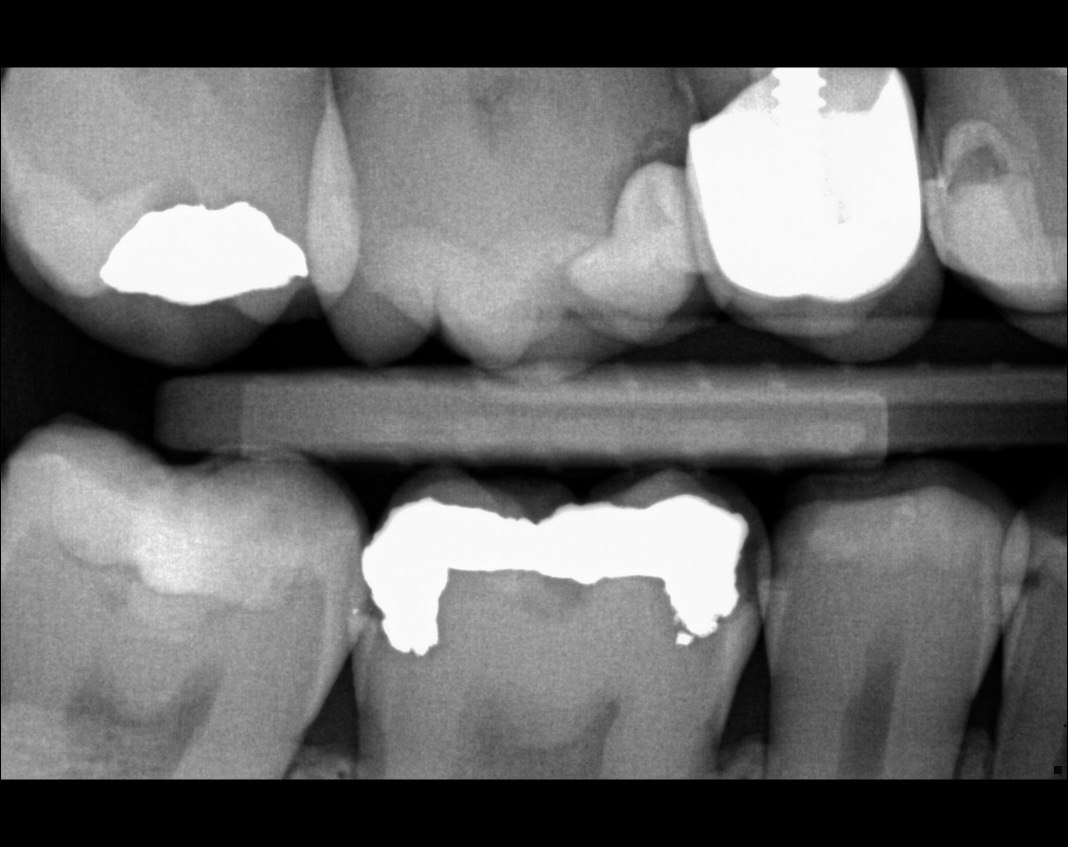

Question 5: Which surface shows recurrent caries?

Question 6: Which surface shows recurrent caries?

Question 7: What are the options associated with the distal surface of the tooth # 2.1 and mesial surface of the tooth # 2.2 respectively?

Question 8: What is the condition associated with the occlusal surface of the tooth # 1.6?

Question 9: What is the condition associated with the mesial and distal surfaces of the tooth # 1.4 respectively?

Question 10: What is the condition of the distal surfaces of the teeth # 1.5 and 1.6 respectively?